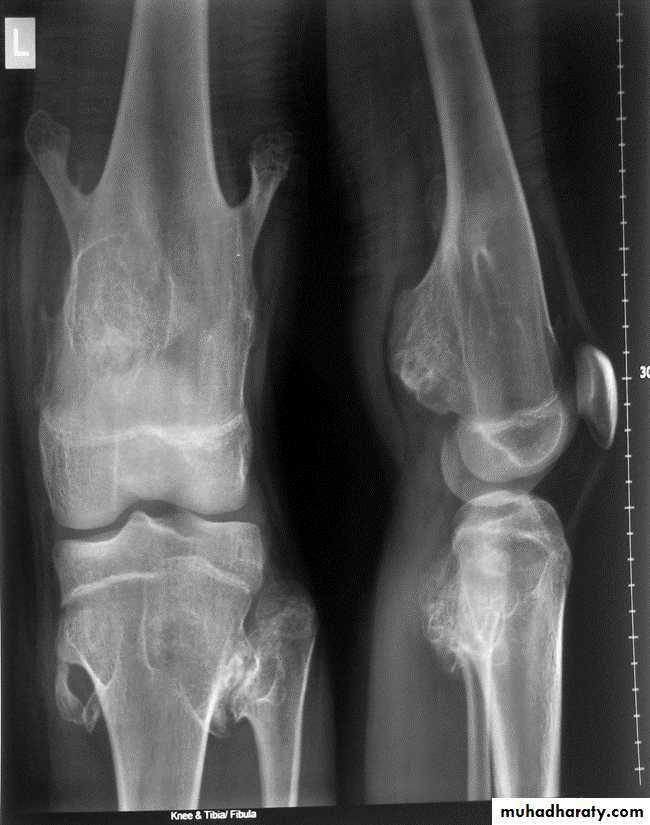

Fibrous Dysplasia :

Defect in the osteoblastic development and maturation as a result of mutation.Types: monostotic & polystotic

Monostotic

Age: 10~30yrs.

Site: ribs, proximal femur, craniofacial bones.

Usually asymptomatic.

Polystotic

Age: at first decade.Usually unilateral, asymptomatic.

Site: femur, tibia, pelvis, cranial bones, spine, feet.

It causes leg length discrepancy,

shepherd crook deformity, facial asymmetry, rib deformity, tibial bowing. Associated with hyperparathyroidism, acromegaly, DM.

• Findings: lytic expansile lesion with typical ground-glass matrix mineralization and sclerosed margin .

Fibrous dysplasia.

AP radiograph of the proximal femur showing a well-defined expanded lesion with typical ground-glass matrix mineralization and a thick, sclerotic margin .Fibrous dysplasia.

A multilocular, partly cystic, expansile lesion

of the midshaft femur is surrounded by a thick rim of reactive sclerosis.